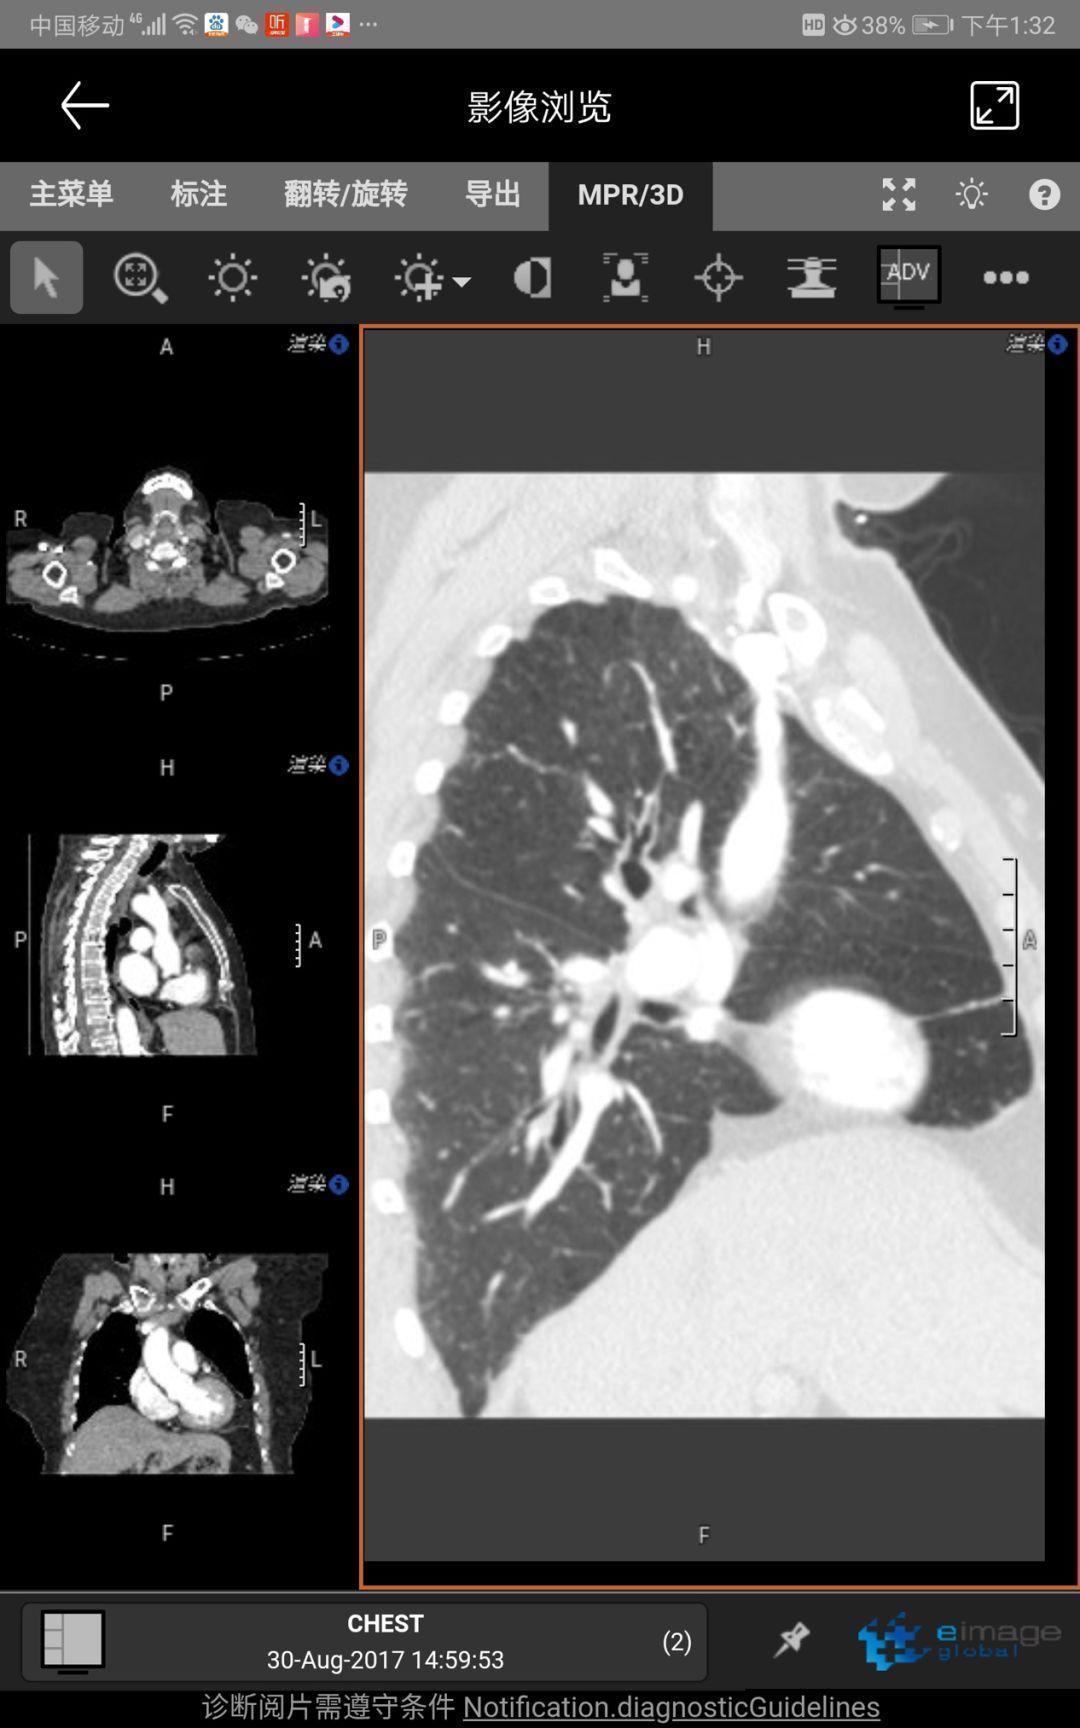

As a branch of eimagelobal.com, the COVID-19 platform integrated a powerful web based DICOM viewer, especially for Lung CT scan images. The MPR and Slice thickness adjustment will help radiologist and pulmonologists to read with greater ease and accuracy.

作為全球影像.com的定制化平臺(tái),國際平臺(tái)集成了功能強(qiáng)大的DICOM影像處理軟件,尤其對(duì)于肺部CT掃描影像,MPR和層厚調(diào)節(jié)功能讓影像醫(yī)生和肺科醫(yī)生更容易、更準(zhǔn)確地閱片。